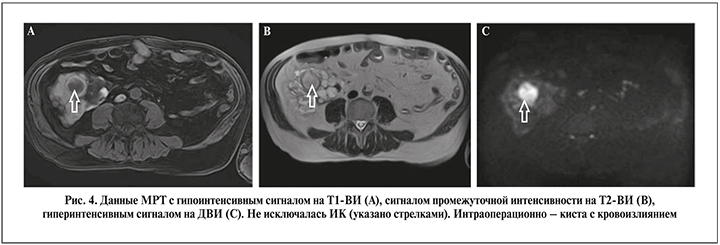

Оценку ДВИ при МРТ изначально стали использовать для идентификации ишемического инсульта [21]. В диагностике заболеваний почек, органов брюшной полости метод начал применяться с начала 2000-х гг. [21, 22]. Заключение о наличии ИК, как правило, делают при снижении интенсивности МР-сигнала на Т1-ВИ, повышении интенсивности на Т2-ВИ и рестрикции диффузии или, говоря другими словами, повышении сигнала на ДВИ [21, 22], однако данные изменения могут наблюдаться и при массе ложноположительных прогнозов [8]. В нашей работе специфичность МРТ составила всего 43,8%. С одной стороны, низкая специфичность была связана с тем, что снижение МР-сигнала на Т1-ВИ, повышение на Т2-ВИ и рестрикция диффузии были характерны не только для ИК, но и для кровоизлияния в кисту. При этом кровоизлияние, судя по клинической картине и результатам гистологического исследования, было либо острое, либо очень старое (рис. 4). Старое кровоизлияние макроскопически представляло собой желеобразную коричневую массу в просвете кисты. С другой стороны, низкая специфичность МРТ могла быть обусловлена невозможностью гистологической идентификации маленькой ИК в значительно увеличенной поликистозной почке.

Магнитно-резонансная томография с использованием протоколов ДВИ выполнена всем пациентам. Заключение о наличии ИК делали при снижении или изоинтенсивном сигнале на Т1-ВИ, усилении сигнала на Т2-ВИ и при повышении сигнала на ДВИ (рис. 1).